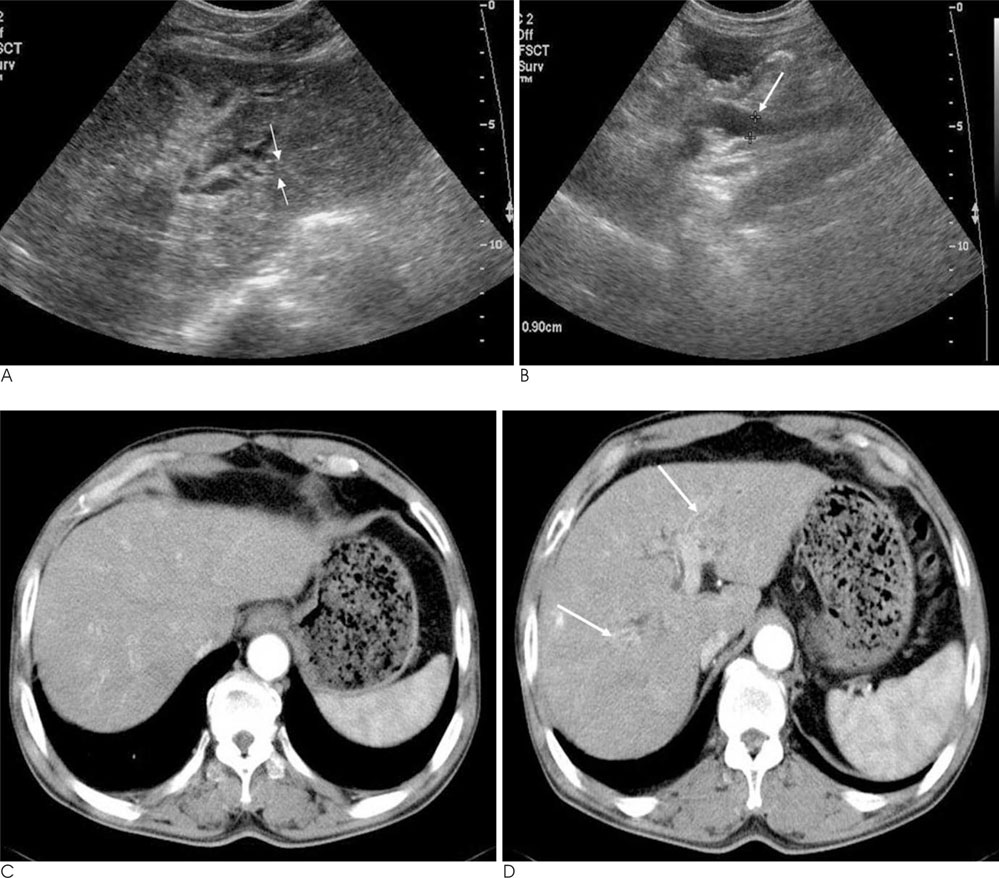

Acute Cholangitis without Biliary Obstruction: Causes and Radiologic Features

The aim of this study is to determine the causes of acute cholangitis without the biliary obstruction and radiological findings.

This study was performed retrospectively. A total of 135 patients diagnosed with acute cholangitis in a clinical setting based on the review of the radiologic findings from an ultrasonogram (USG), computed tomogram (CT), or magnetic resonance images (MRI). Among them, patients with a biliary obstruction as a result of a stone, tumor, lymph node, stricture were excluded. A total of 31 patients had acute cholangitis without a definite biliary obstruction. We analyzed their causes and imaging features with the USG and CT image.

The causes of acute cholangitis without biliary obstruction included Clonorchis sinensis cholangitis in 15 cases (48%), post-operative swelling after gastrojejunostomy, pylorus preserved partial duodenectomy, and choledochojejunostomy in 7 cases (22.6%), recent spontaneous passage of a distal CBD stone in 3 cases (9.7%), compression effect by the large duodenal diverticulum in 2 cases (6.5%), and unknown causes in 4 cases (12.9%).

Acute cholangitis may be associated without a distal biliary obstruction. USG, CT, or MR imaging can provide precise information as well as help to differentiate the causes of acute cholangitis.